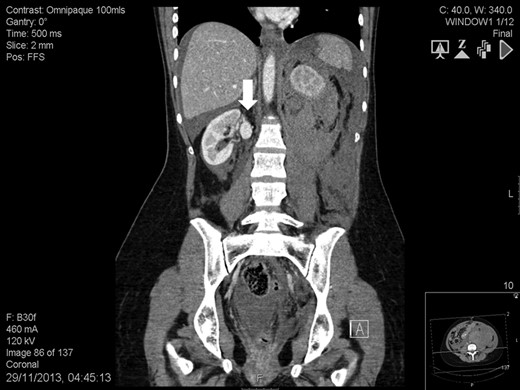

A 41-year-old woman, 21-week pregnant, presented to the Emergency Department with left-flank pain, hypotension (100/60 mmHg) and tachycardia (95 bpm). Blood tests were: haemoglobin 7.3 g/dL, leukocytosis 23.4 cell × 109/L, lactate 3.6 mmol/L, base excess −8.4 mol/L and serum creatinine 82 mmol/L. Abdominal ultrasound was normal but foetal monitoring demonstrated a drop in heart rate suggestive for impending demise. Placental abruption was suspected and following resuscitation she was brought to theatre. We found a large left-sided retroperitoneal haematoma and a non-viable foetus. Exploration also revealed a ruptured left RAA and a contralateral RAA. At this point, it was felt a percutaneous approach would have been more appropriate. Contrast-enhanced computed tomography showed a massive retroperitoneal haematoma, a ruptured left RAA (Fig. 1), and an intact right-sided RAA measuring 2.2 cm (Fig. 2). Under selective angiography, the aneurysm was embolized and the bleeding controlled [3]. Recovery was rapid but a DMSA scan performed 2 weeks later, demonstrated reduced function in the treated kidney (37%). The risk of rupture of the right RAA was deemed significant and a plan for repair was made. The lesion was saccular, wide-necked and located at the artery bifurcation thus preventing endovascular treatment. We opted for hand-assisted retroperitoneoscopic nephrectomy, ex-vivo repair and autotransplant.

Abdomen contrast-enhanced computed tomography scan showing an intact 2.2-cm right renal artery aneurysm (white arrow).